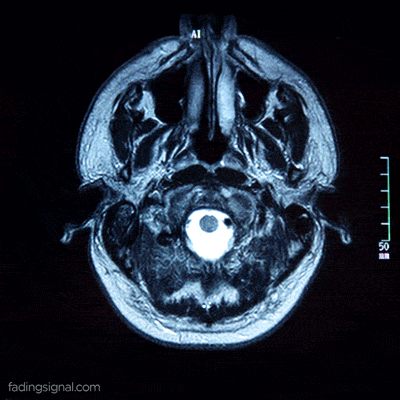

Dette bekræftes af forskning, der blev offentliggjort i 2017 i tidsskriftet Nature. Ved hjælp af MR-scanning kunne det forskerhold, der gennemførte denne undersøgelse, observere ændringer i nogle dele af hjernen, der er relateret til orientering.